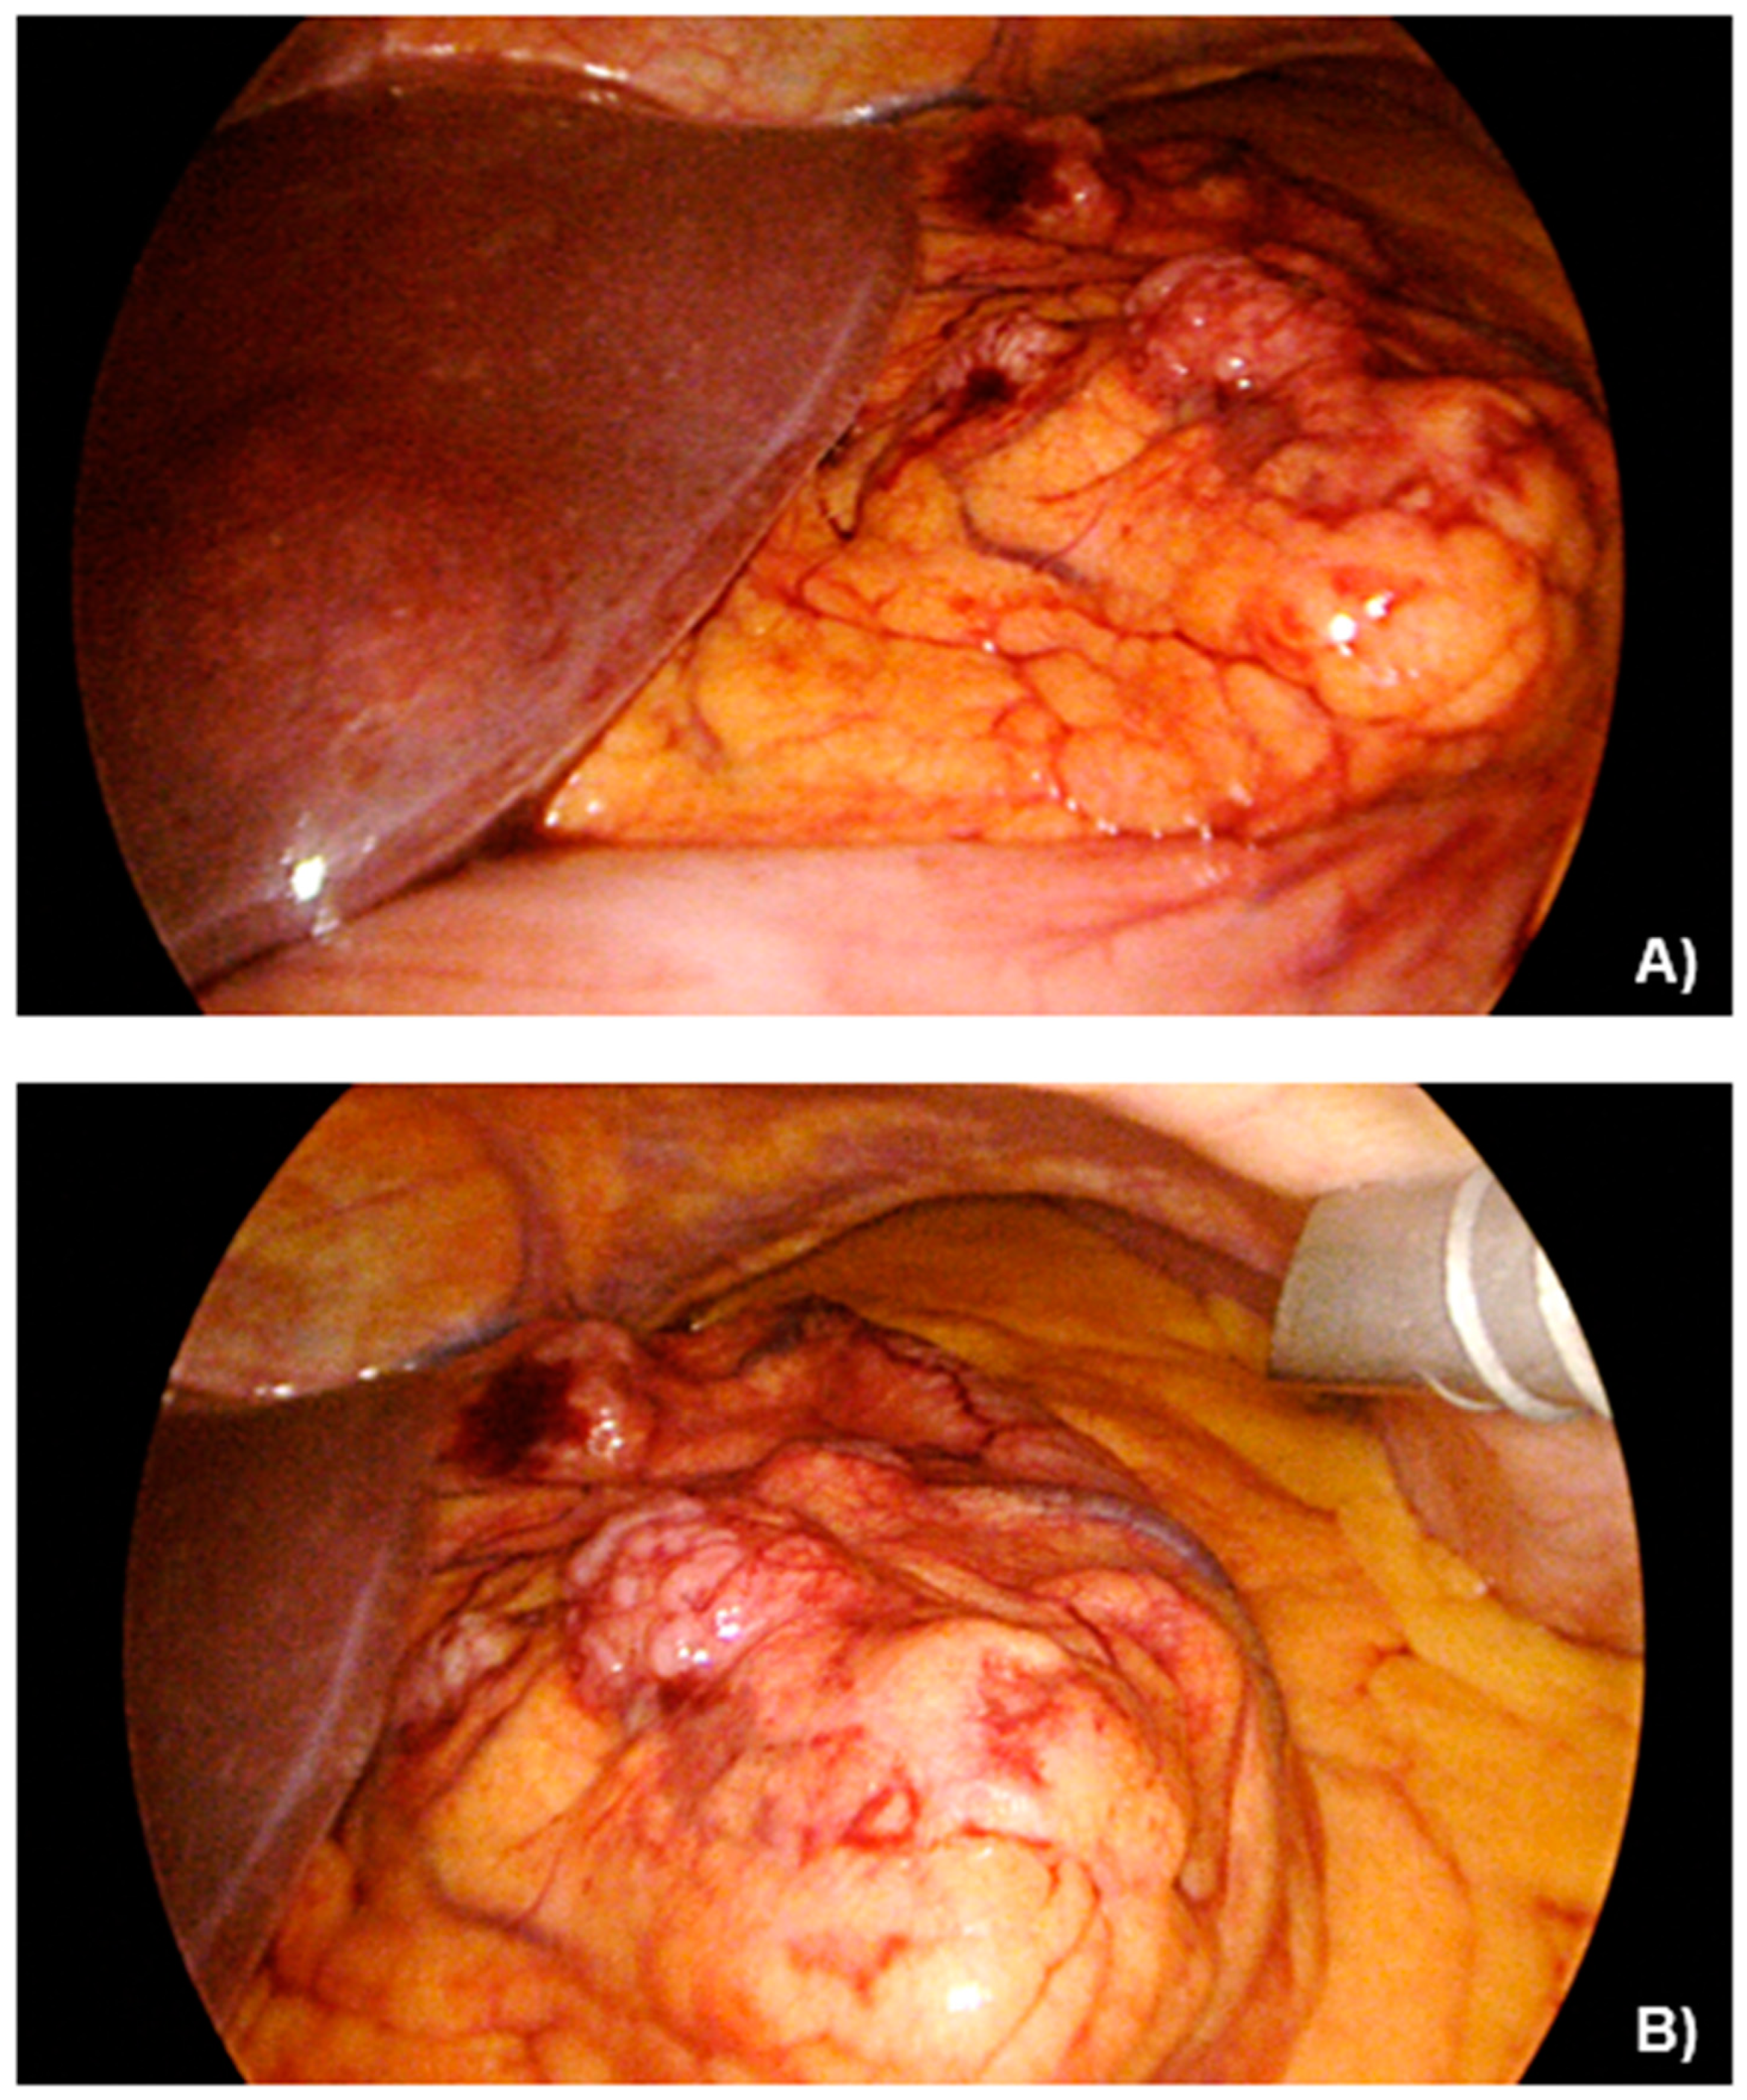

2.2. Case Presentation

3.1. Case Management